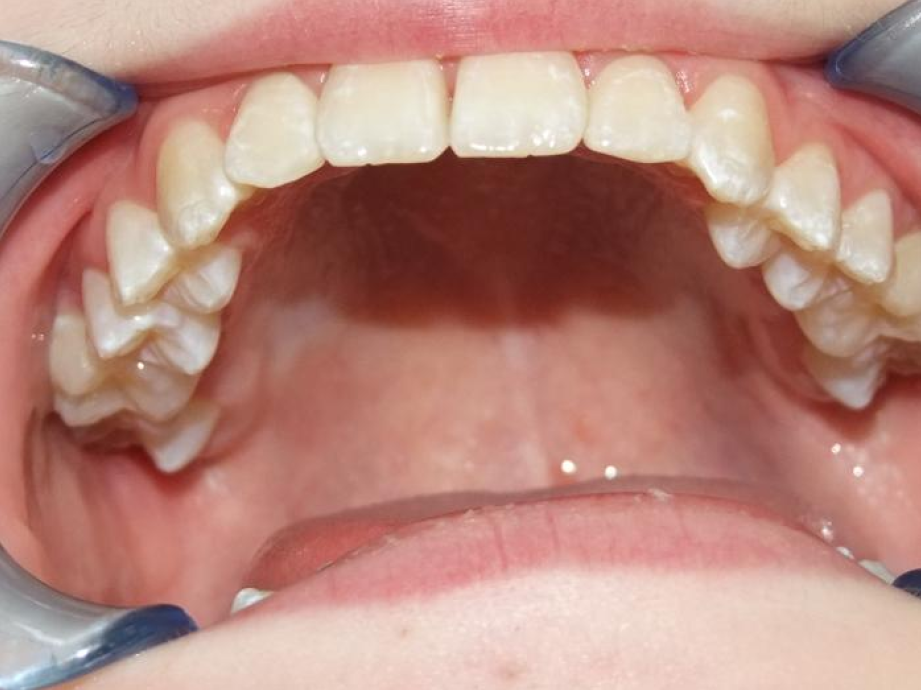

eindfoto

Leeftijd bij aanvang: 9 jaar

1-6 Bonded Hyrax + volledig vast onderkaak + TransForce onderkaak

7-13 Twin Block

14-28 volledig vast onder- en bovenkaak + rotator

Retentie: Wrap-Around

Leeftijd bij retentie: 12 jaar